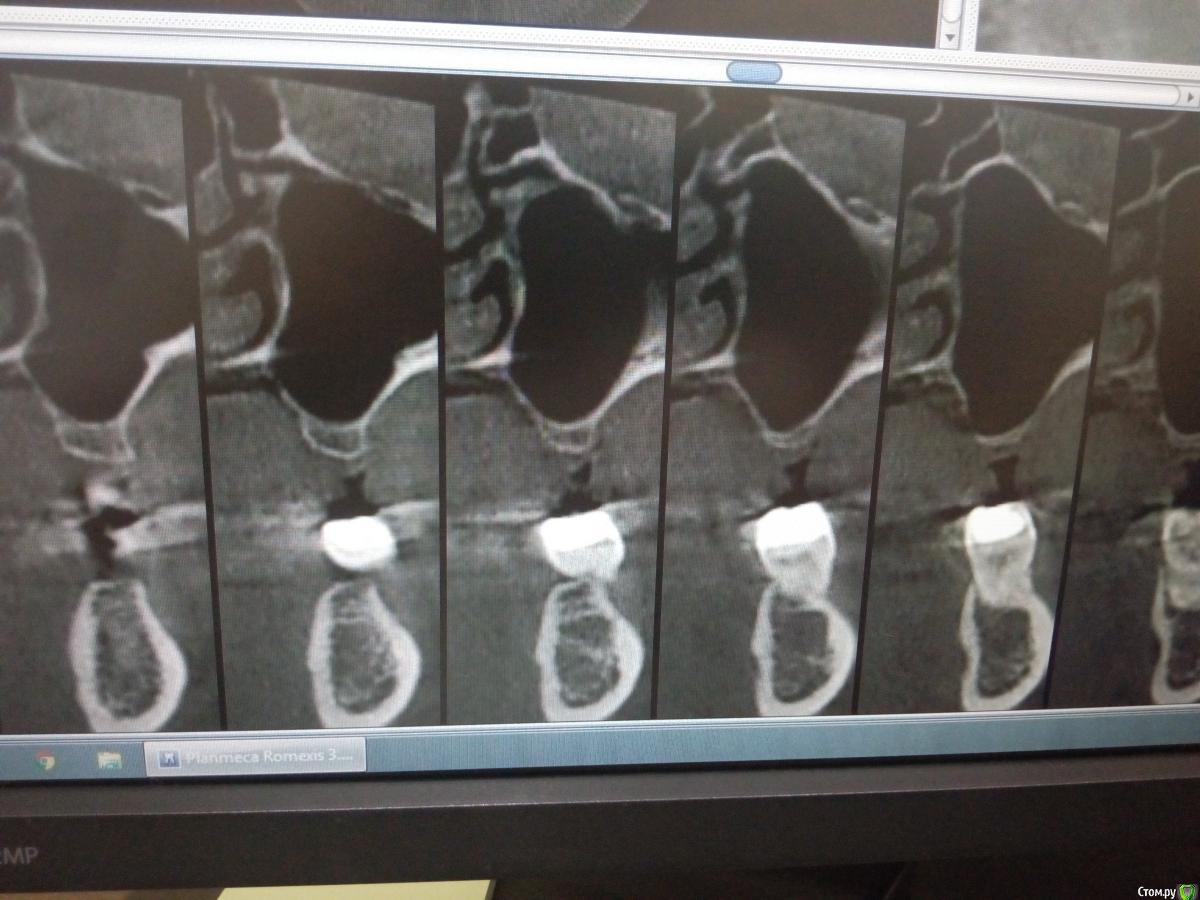

Sampson Опубликовано 14 августа, 2018 Поделиться Опубликовано 14 августа, 2018 (изменено) В феврале провел первый свой открытый синус.Снимок доПосле операцииНеделю назад пришла на контроль. Изменено 14 августа, 2018 пользователем Sampson Ссылка на комментарий

колесников Опубликовано 14 августа, 2018 Поделиться Опубликовано 14 августа, 2018 (изменено) То что вы отслоились небной-это превосходно! Обычно,по началу,многие побаиваются углубляться и дальше окна не ходят. Но я бы рекомендовал ещё мезиодистально отслаиваться. Теперь спереди и сзади от графита ямы для скапливания слизи ,причина пролиферации шнейдеровой. Изменено 14 августа, 2018 пользователем колесников 2 Ссылка на комментарий